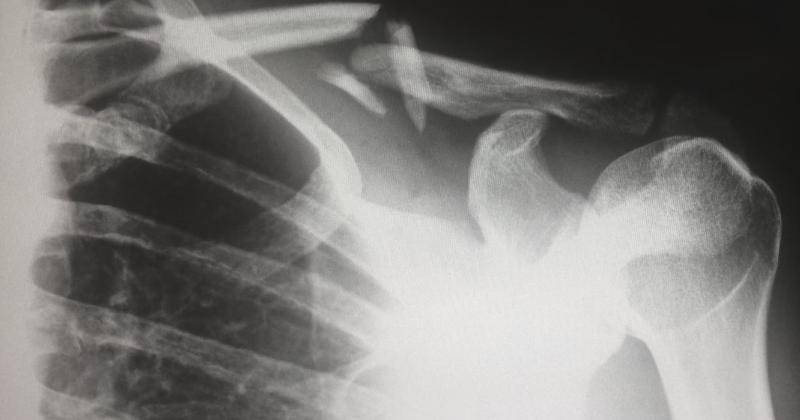

Cara Mendiagnosis Nursemaid Elbow

Jika anakmu menunjukkan gejala Nursemaid Elbow, sebaiknya segera bawa mereka ke dokter. Dokter akan memeriksa lengan anak dan mungkin tidak perlu melakukan X-ray, kecuali jika ada kemungkinan patah tulang. Biasanya, dokter hanya perlu meraba dan memutar lengan anak secara lembut untuk memeriksa rasa sakit dan rentang gerakan lengan.